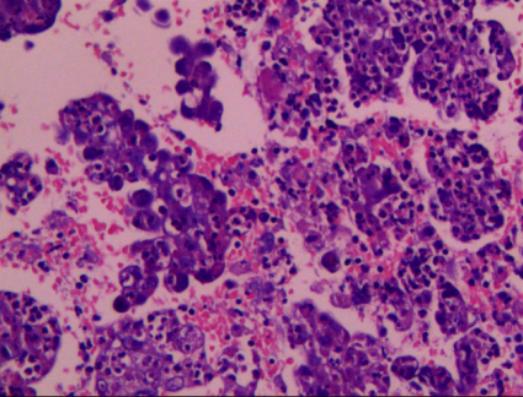

成功获取病理标本

病理结果:肺腺癌